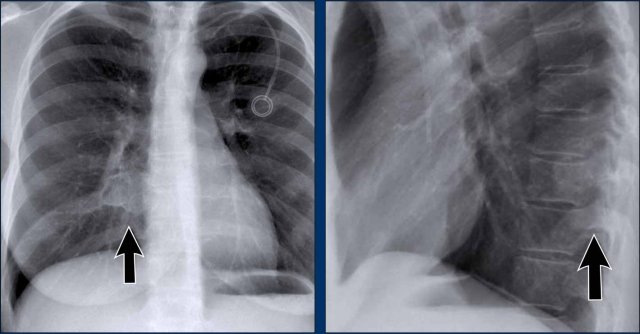

Case Example: Subtle Signs of Congestive Heart Failure

Begin by reviewing these current chest radiographs.

Based solely on these images, one might suspect congestive heart failure (CHF), though the findings are subtle.

Now review the previous study…

Scrolling between the current and prior films significantly increases diagnostic confidence in your diagnosis of congestive heart failure.

Key comparative findings include:

- Cardiac size: Slightly increased compared to the previous study; however, cardiomegaly was already present.

- Pulmonary vasculature: Mild vascular engorgement suggesting elevated pulmonary venous pressure.

- Interstitial markings: Subtle signs of interstitial edema .

- Pleural effusions: Bilateral small effusions, with subtle changes in the inferoposterior borders of the lower lobes, suggesting fluid accumulation.